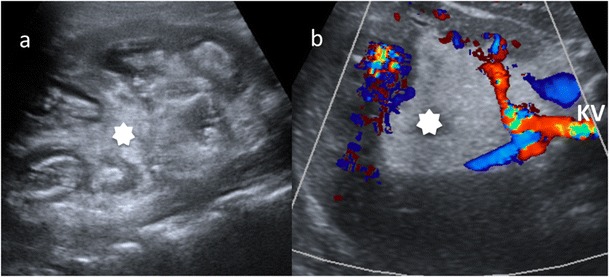

Fig. 7.

Diffuse XPN in left kidney. a Longitudinal ultrasound shows important inflammatory exudate and fatty proliferation (white asterisk) inside the kidney. b Transverse Doppler ultrasound shows kidney vessels (KV) passing through the inflammatory and fatty proliferation (white asterisk)